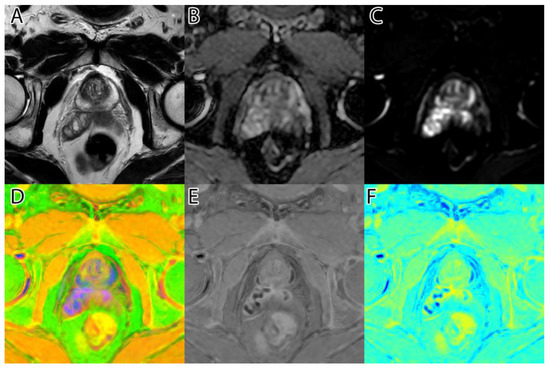

The second step was to compute the inversion of T2WI and ADC, thus obtaining the area of interest (tumor) represented by higher intensity values, as seen in Figure 1D,E. For this, we subtracted the actual image values from the maximum of 255.

Figure 1. Sample image: (A)—T2WI; (B)—ADC; (C)—DWI; (D)—inverted T2WI; (E)—inverted DWI; (F)—RGB images resulting from image fusion of (CE).

The third step was to combine the three images into an RGB (red, green, blue) image. T2WI was used for the red channel, ADC was used for the green, and DWI was used for the blue. The resulting image can be seen in Figure 1F.

The algorithm was used on all 204 images and computed the tumor intensity image. A sample from the original data, and the resulting fused image, can be seen in Figure 1.